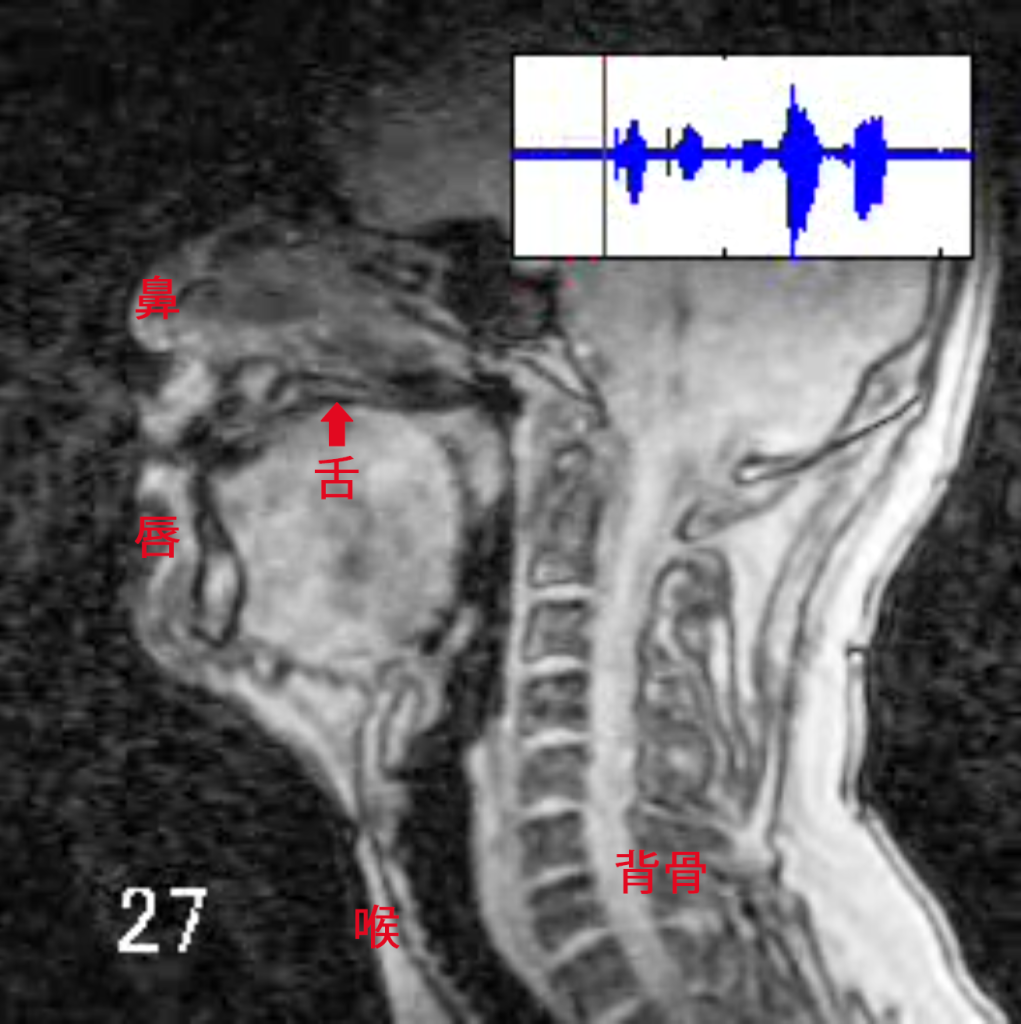

川原 これはMRIっていうんだけれども、知ってる? 病院で使うものだから、あまり馴染みがないかもしれない。だけど音声学者はMRIに入って、人間が発音するときに何が起きているんだろうというのを撮影したりするの。こっちが「か・き・く・け・こ」を発音した時の様子。

MRIの見方の説明をしないとね。この人は左を向いていて、顔の断面図が映っています。真ん中に映っているのが舌。「か・き・く・け・こ」を発音するときに、舌がどう動いているか、ちょっと見てみて。この舌の奥のほうが動いているのがわかる?

川原 「か」は舌の後ろ側が動くんだったね。じゃあ、「がぎぐげご」はどうだろう? MRIを見てみようか。「かきくけこ」とほとんど一緒だね。じゃあ「か」と「が」は何が違うのっていう話になる。